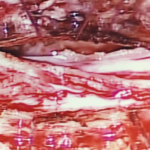

頸椎6/7節椎管位置長了一個1.6cm腫瘤嚴重地壓著脊髓

頸椎6/7節椎管位置長了一個1.6cm腫瘤嚴重地壓著脊髓

腫瘤嚴重地壓著脊髓

割除椎管腫瘤